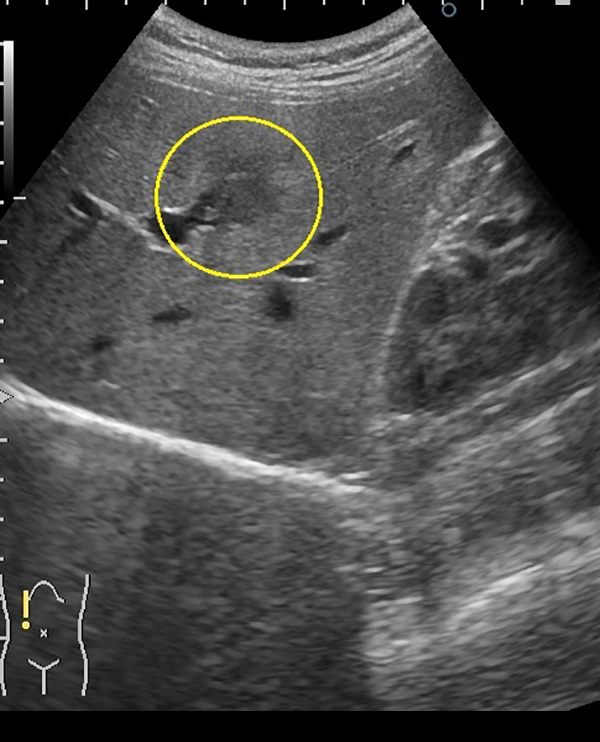

腹部超音波検査画像の解説

①肝内胆管癌

1. 肝臓の中央やや上寄りに周囲より黒っぽい不整な領域を認めます。

2. ドップラーエコーで動脈血流を認めました。

3. この時点で径16.9×16.9mmでありステージI期と考えられます。

このサイズで胆管癌が見つかることは非常にまれです。